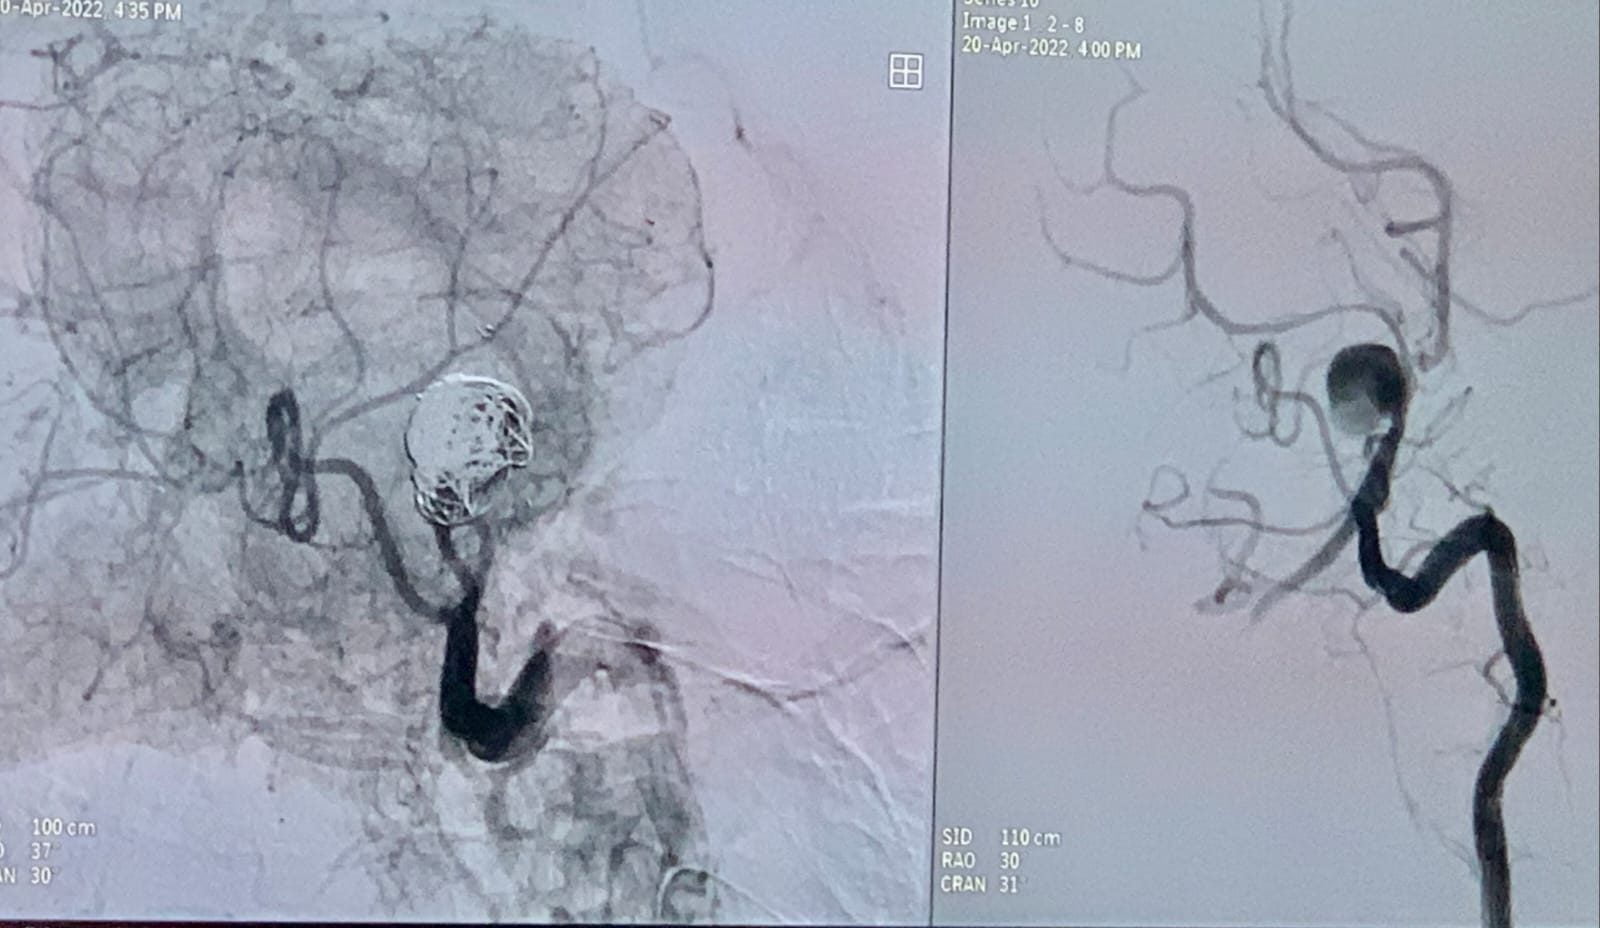

Bhubaneswar: A team of doctors of Shanti Memorial Hospital successfully treated a 23-year-old woman of rare brain aneurysm.

According to the hospital’s doctors, the patient had sudden severe headache and collapsed on the floor. She was rushed to Shanti Hospital where the doctors carried out necessary investigations and found a very large ruptured brain aneurysm measuring 22 mm in the mid brain.

This is a life threatening condition and needed immediate attention, said the team of doctors. The team headed by Dr Sibasankar Dalai and including Dr Sreejoy Patnaik, Dr. Rekha Das, Dr Avijit Prusty, Dr P Nath and Dr Priya Tripathy conducted the emergency aneurysm coiling.

A successful coiling of the ruptured 22 mm aneurysm was done over several hours by the team of experts and a precious young life is saved.

Treatment of brain aneurysm involves opening the brain, finding the aneurysm and clipping it. Clipping a brain aneurysm is often complicated and involves serious repercussions. Hence, medical science has moved in the direction of minimally invasive treatment of brain aneurysm called “coiling of brain aneurysm”.

Coiling of brain aneurysm is done through a single puncture in the leg blood vessel. The coiling operation is the most modern way to treat brain aneurysm and this is done without opening the skull. This has high success rate and least compilation.